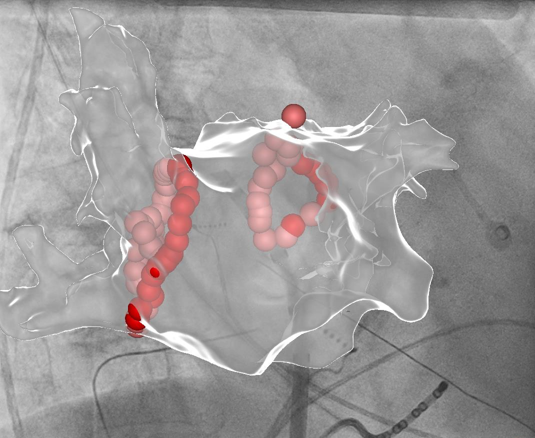

Vorhofflimmer Therapie - persönlich und individualisiert

Vorhofflimmern ist mit Abstand die häufigste Rhythmusstörung - jeder 3. Europäer wird im Laufe seines Lebens daran erkranken. Erfahren Sie mehr, wie wir Vorhofflimmern mit modernster Kathetertechnik behandeln - egal, ob Sie seit kurzem erkrankt sind, oder die Erkrankung bereits chronifiziert ist. Wir finden für Sie die richtige Technologie!

Links: Ultraschallbild eines Herzens, rechts: farbcodierte Substratkarte des Herzens